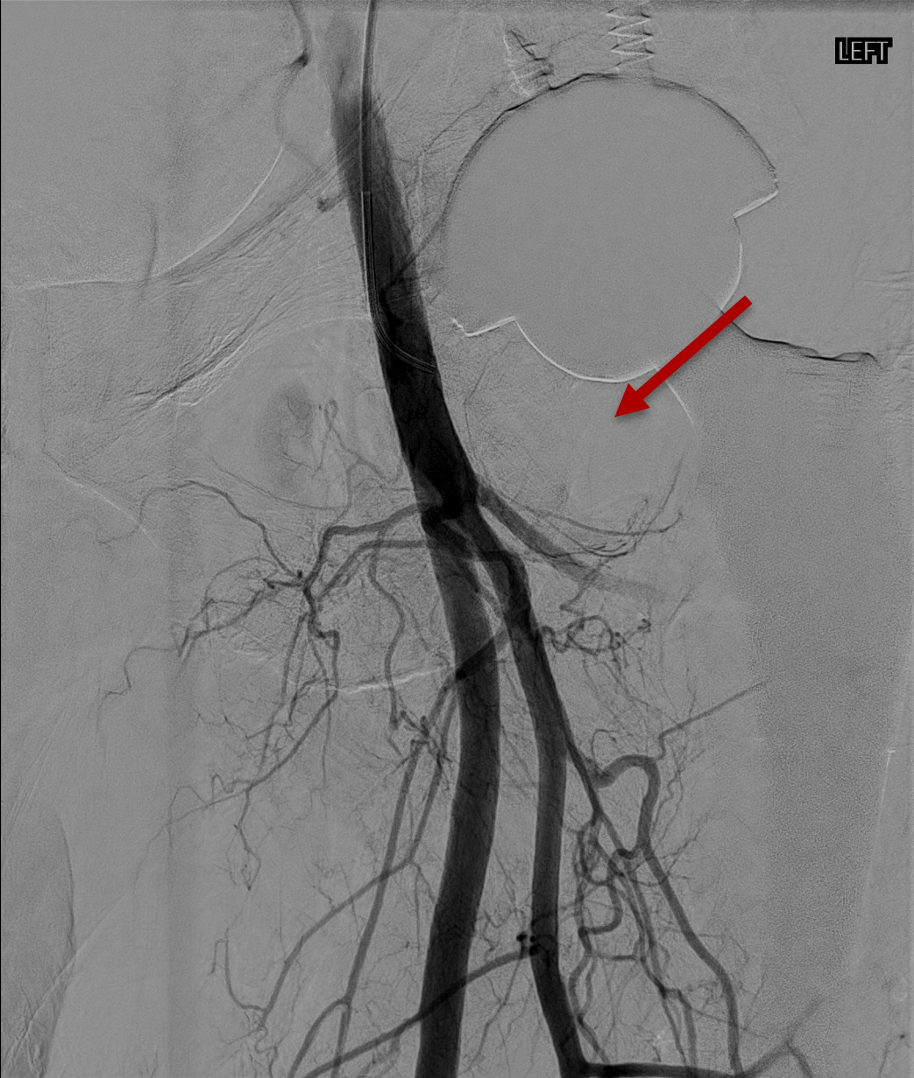

TAME works by cutting off the blood supply to these abnormal vessels. Using a fine catheter inserted through a small artery — typically at the foot or wrist — an interventional radiologist navigates to the arteries supplying the affected joint or tendon. Contrast dye is injected and X-ray images are taken to identify areas of abnormal blood vessel proliferation, which appear as a characteristic "blush" — a cloud-like staining pattern distinctly different from normal vascular anatomy.

Only arteries showing this abnormal blush are treated. A small amount of embolic material is injected to block the pathological vessels. Normal arteries supplying healthy tissue are left untouched.

Knee osteoarthritis is the most established and extensively studied application for TAME. The knee joint is supplied by up to six genicular arteries forming a network around the joint. During the procedure, each of these arteries is examined with contrast injection. Only those showing abnormal blush — indicating active inflammation — are treated.

Pre-embolisation angiogram

Marked blush in the medial compartment. Indicating severe chronic inflammation, formation of neo-vessels and neo-nerves.

Post-embolisation angiogram

Complete pruning of the abnormal blush. Preservation of the main vessel stems.